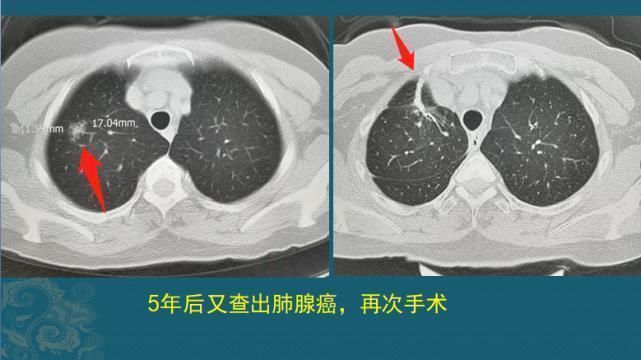

癌细胞还算实诚,只转移了肝脏,其它地方没发现。根据病人的整体状态,选择了介入治疗,用碘油和化疗药封堵血管,杀灭癌细胞,之后5年没复发!但5年后又发生了右侧肺腺癌,呈混合磨玻璃结节,边界清晰,1.7cm:

文章插图

这位女士经过5年的调养,身体已经很好,完全可以耐受手术,今年又做了肺癌根治术。一位中年女性,在6.5年时间里先后经历乳腺癌手术、肝转移瘤手术、肺癌手术,依靠规范治疗+良好的心态(其实就是没心没肺),就这么走过来了!通过胸部CT外围的脂肪线我们会发现,她的体重保持得很好!可能还需要稍微减减肥……